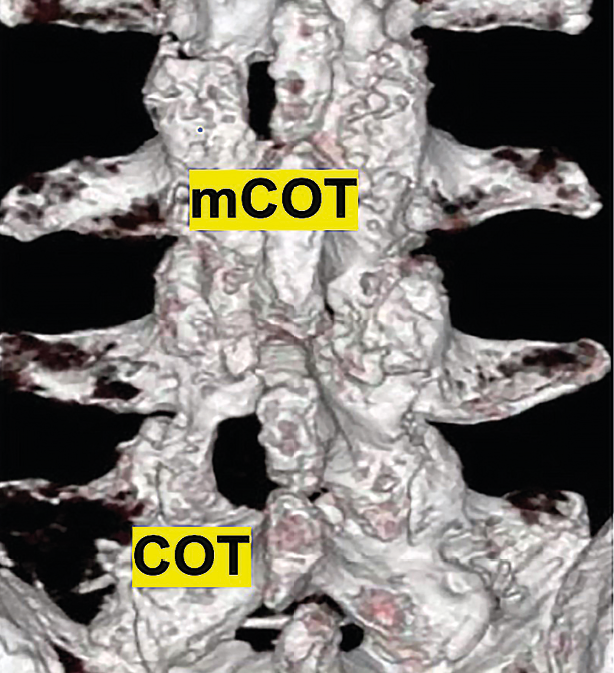

Decompression of lumbar spinal stenosis in medialized cross-over technique (mCOT):

Flattening the top of the spinous process (if necessary)

Exposure of the spinolaminar connection. Removal of bone tissue from the deeper half

Decompression of the contralateral dural sac and root.

Decompression of access side.